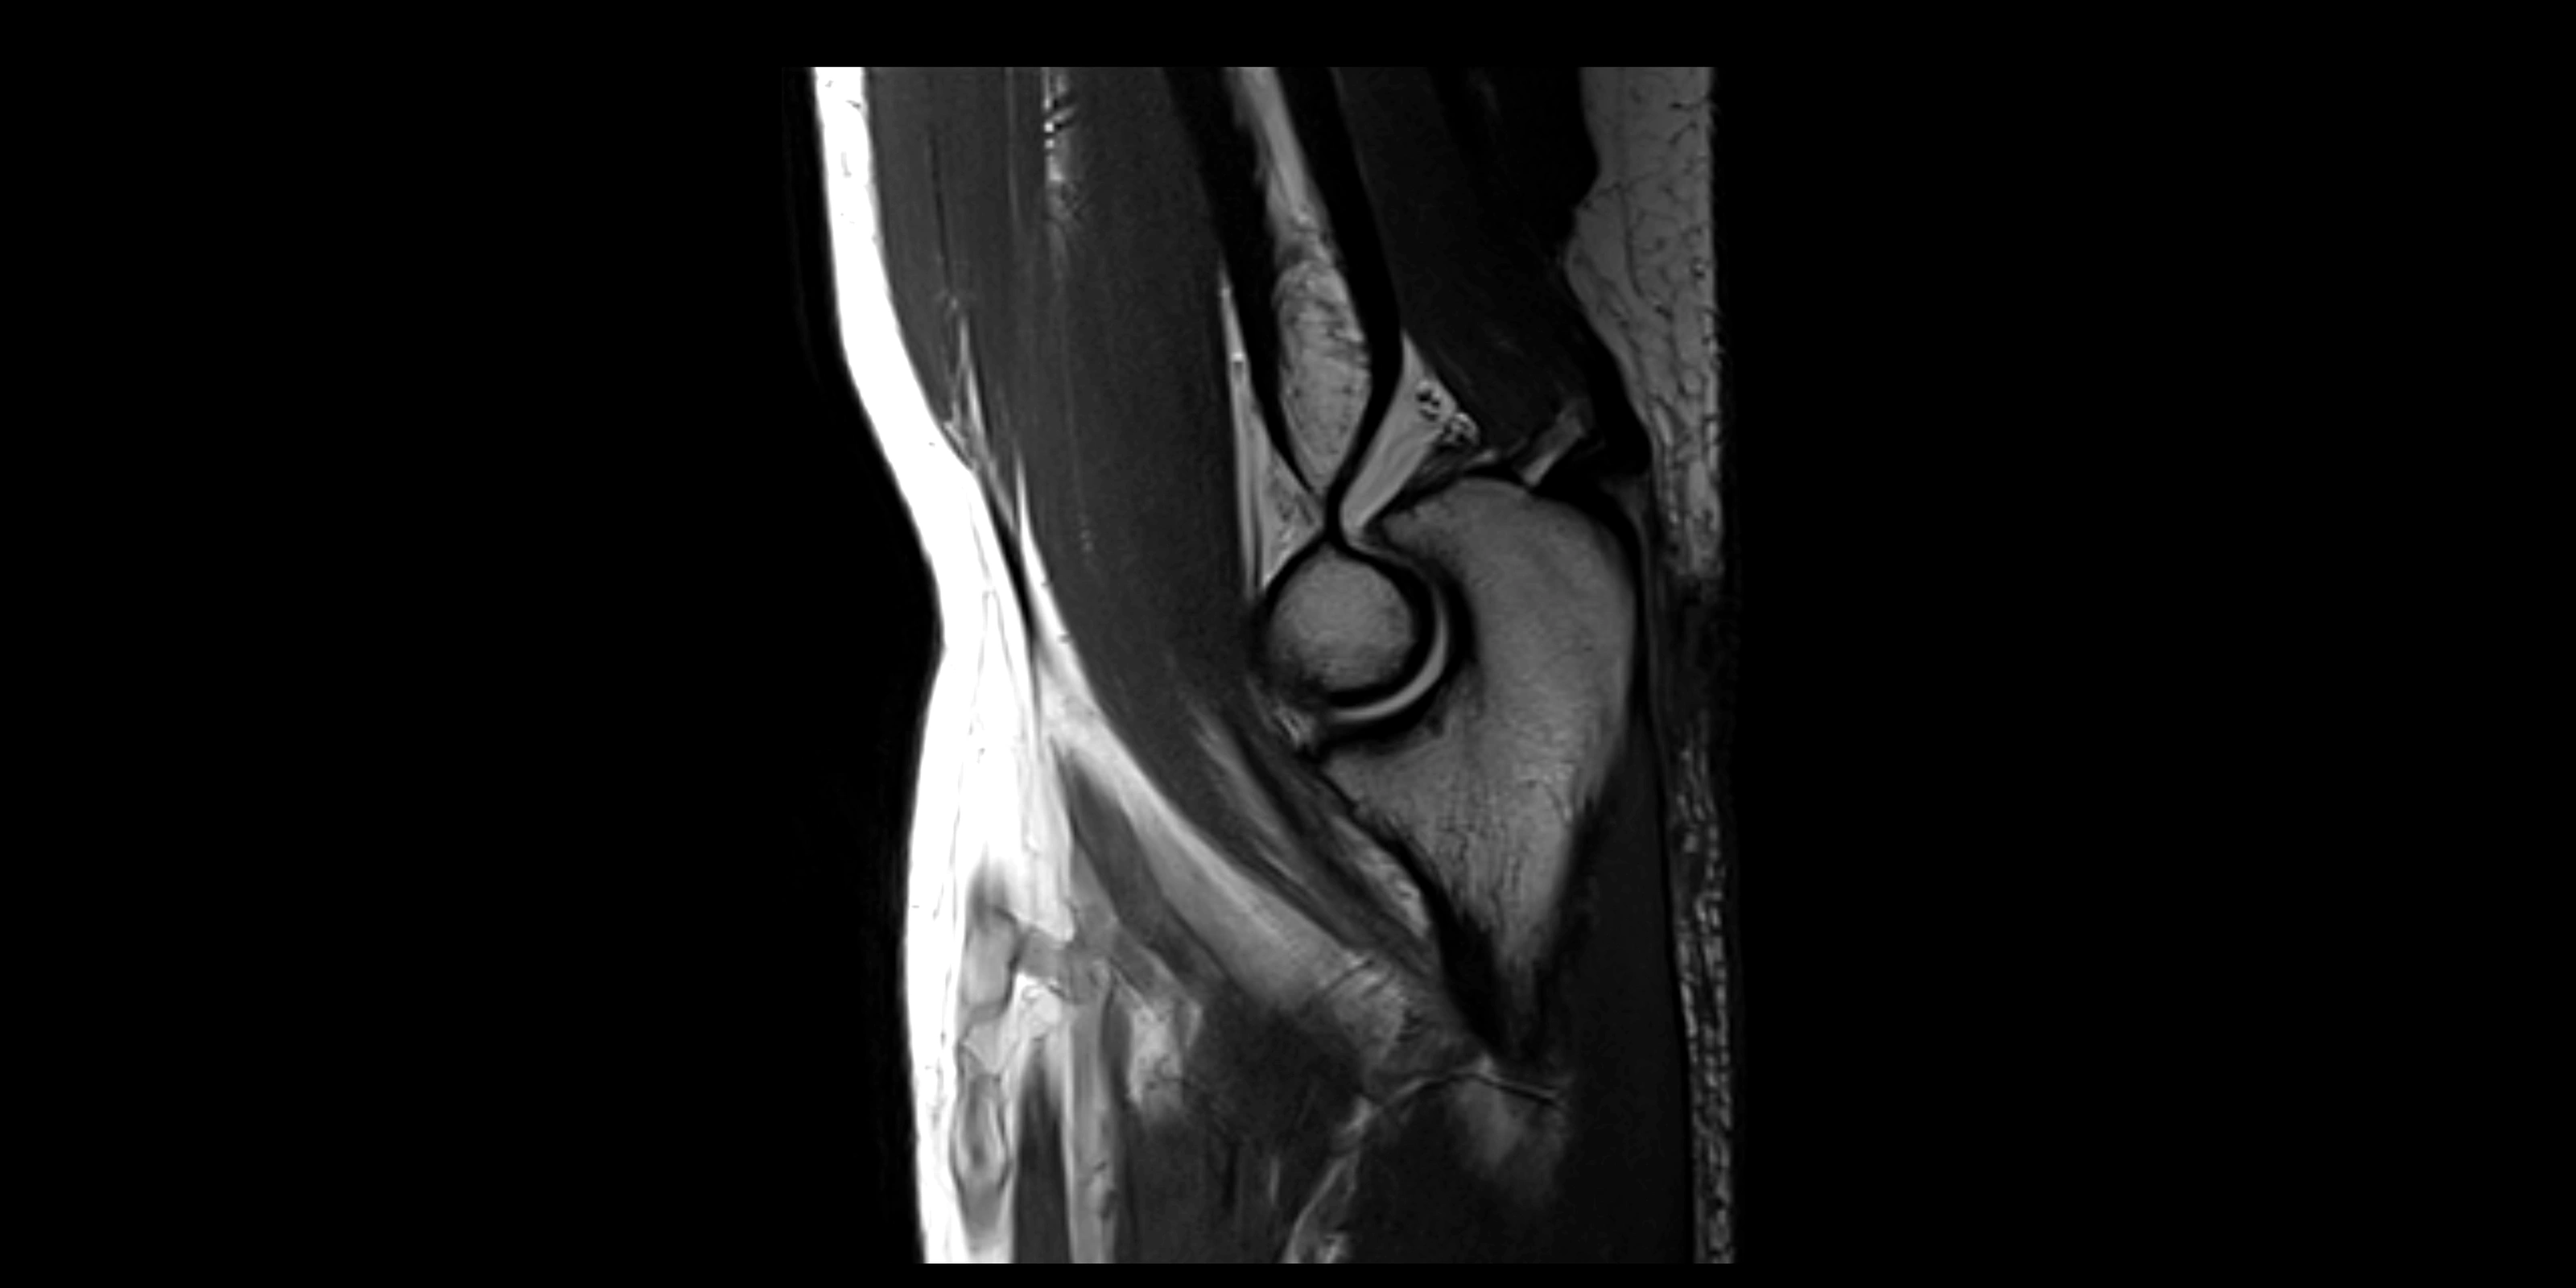

MRI images

image